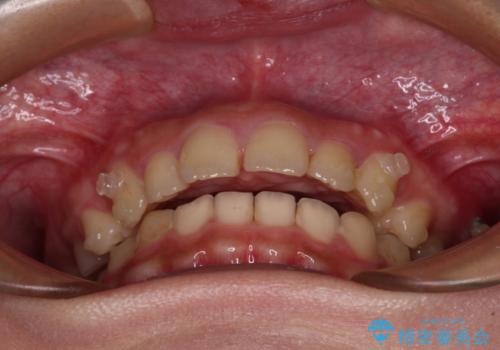

- 深い咬み合わせと上顎前歯の突出感を気にして来院された患者様です。

正面や横からの写真ではきれいに治っており、患者様は大変満足のいく仕上がりとなりましたが、深い咬み合わせの改善は不十分で、奥歯の咬み合わせも改善させることができませんでした。